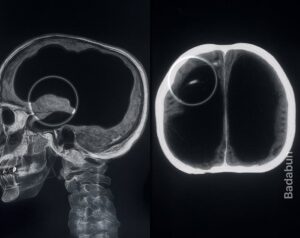

Un hombre en Francia fue al hospital por una simple molestia en la pierna… y terminó dejando en shock al mundo entero. Cuando los médicos vieron su escáner, no podían creerlo: su cráneo estaba casi vacío. El 90 % de su cerebro parecía haber desaparecido. Aun así… el hombre vivía una vida completamente normal. Tenía […]